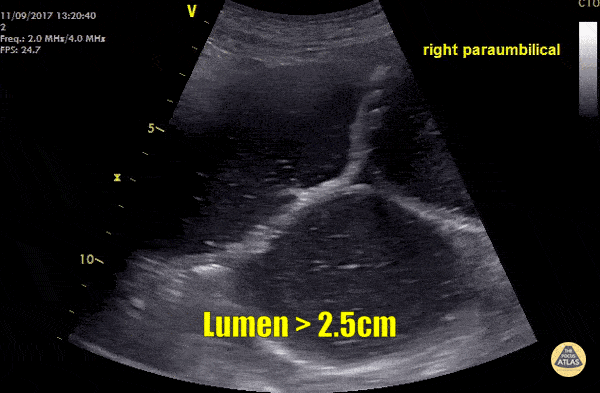

These images were recorded from an elderly lady with abdominal pain and vomiting. Small bowel lumen is dilated more than 2.5cm and there is reduced peristalsis within the lumen - these sonographic signs are consistent with small bowel obstruction (SBO). Other signs of SBO include the presence of hyperechoic material moving back and forth within the bowel lumen and free fluid between the loops of bowel (Tanga sign). Images by Dr. Rory Whelan Submitted by Dr. Cian McDermott - Dublin, Ireland